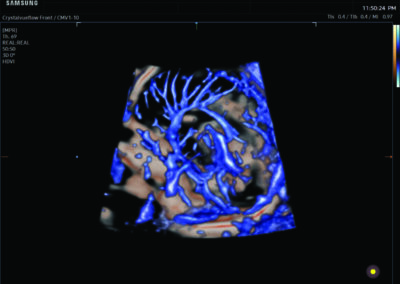

Procedural Services

Comprehensive, advanced and expert MFM care for high-risk pregnancies